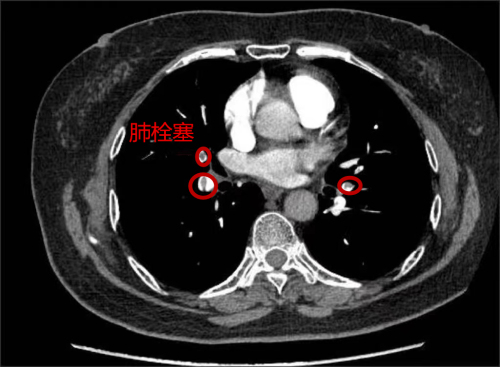

治疗前,肺动脉部分血管造影下可见栓塞

家住长沙的73岁刘女士,3个月前因“反复胸痛”先后于多家医院就诊,因曾怀疑为冠心病,虽服用了治疗冠心病药物,但症状未见好转,后来到湖南省人民医院心内四病区就诊。在仔细询问病史后,心内四病区陈美娟主任医师认为其胸痛可能是肺栓塞所致。经肺动脉CTA、双下肢静脉彩超检查,患者被确诊为肺栓塞。为防漏诊,患者进行了冠脉造影检查,结果显示冠脉光滑,没有冠心病。5月5日,刘女士在服用了抗凝药物治疗3个月后,复查肺动脉及双下肢静脉未见血栓,胸痛症状明显好转。